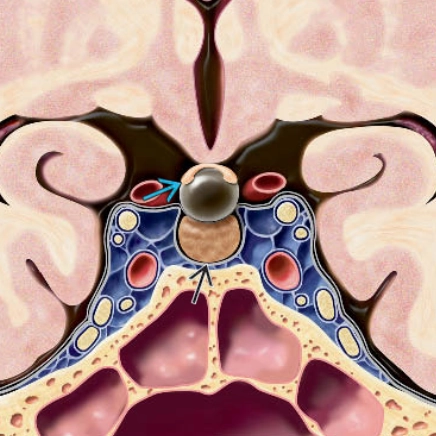

• Nhồi máu não do thiếu máu cục bộ (Ischemic stroke)

• Nhồi máu lỗ khuyết (Lacunar Infarction - LI)